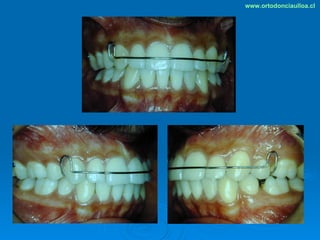

Este documento presenta dos casos clínicos de pacientes que recibieron tratamiento de ortodoncia. El primer caso fue de una paciente femenina de 14 años con apiñamiento dental y mordida cruzada que fue tratada mediante extracción de premolares y alineamiento dental. El segundo caso fue de un paciente masculino de 14 años con clase II esqueletal y desarmonía dentomaxilar que fue tratado con extracción de premolares y corrección de mordida. Ambos casos mostraron mejoría después de 3 años de tratamiento.